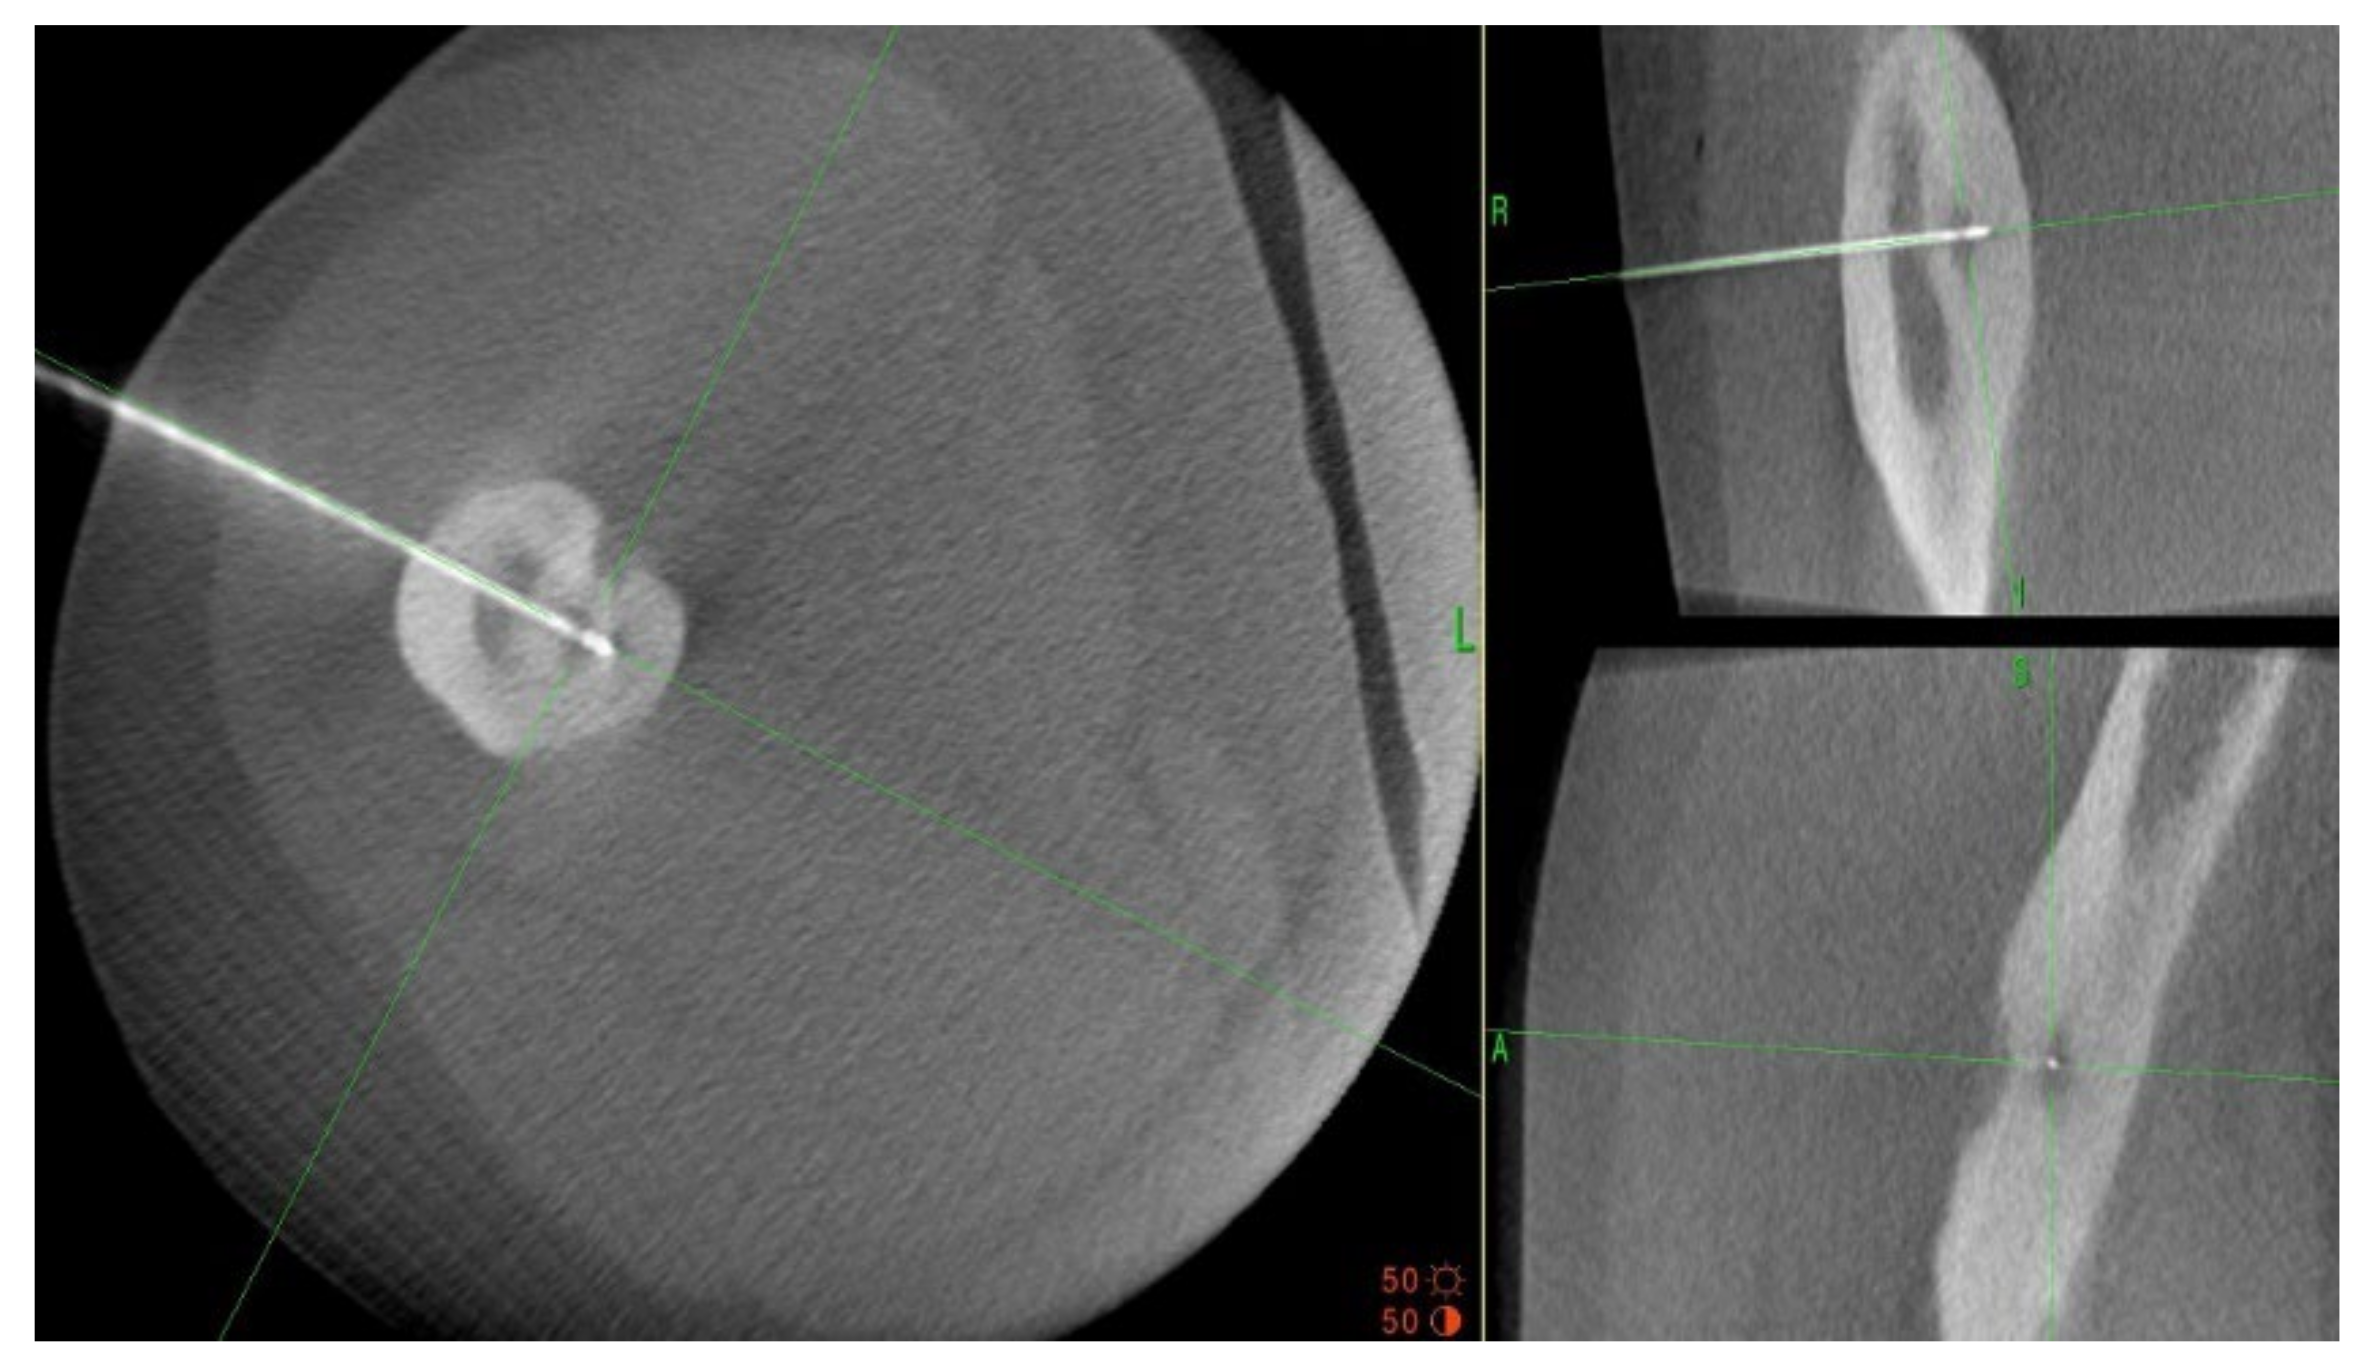

A 35-year-old male patient presented with a diagnosis of inadequately treated osteoid osteoma for two years. The patient informed of pain at night and during the day after exercise or prolonged immobilisation of the limb (sedentary work). The suspicion of OO in the right distal metaphysis of the right femur (a nidus size of 12 × 4 × 4 mm) was raised from the first X-ray examination and a CT scan performed two years earlier. Pain was localised exclusively to the right limb; however, on examination, an incidentaloma was detected in the posterolateral part of the femoral diaphysis on the opposite side with an initial suspicion of a proliferative process. Following an MRI scan of the left knee joint, a suspicion of a non-ossifying fibroma in the healing phase was raised. In a subsequent examination, bone scintigraphy was performed. A focus of pathological tracer accumulation in the right femur was described as a suspected benign lesion, but proliferative disease could not be excluded. After further additional examinations, the patient was qualified for resection of the right femoral tumour. The resection procedure was performed, and the specimen was collected for histopathological examination. After surgery, there was no improvement in terms of pain, and extension contracture of the knee joint (flexion to a level of 120 degrees) developed. The histopathological examination suggested a diagnosis of haemangioma. After further clinical examinations and additional examinations (including a CT scan) (Figure 3), the absence of the features of osteoid osteoma recurrence was described, and pain was associated with the features of a femoropatellar joint injury. Histopathological specimens were re-analysed with the result that there were no features of malignant cells or osteoid osteoma. Over the following months, persistent night pain extending to the anterior surface of the patella and right lower leg was reported. On clinical examination, flexion of the right knee with pain in the medial distal part of the thigh occurred. The subsequent diagnostic process at a rheumatology outpatient clinic suspected gout. The patient was treated with colchicine for several months without any signs of improvement. A second look at the CT scan confirmed a diagnosis of persistent focus of OO. The patient was admitted to the Department of Orthopaedics with muscular atrophy of the right lower limb, impaired mobility (limitation of knee joint flexion of approximately 30 degrees), pain VAS of 6, to perform thermoablation of the lesion resection site. The patient underwent the above procedure under general anaesthesia (Figure 4). On examination the day after surgery, there was a significant reduction in pain (VAS score of 1). On examination 3 months after surgery, there was complete resolution of pain (VAS scope of 0), active flexion of the knee joint without pain, and the patient’s return to activities of daily living. He was recommended to undergo active rehabilitation to restore full limb function.

Figure 4.

Intraoperative photographs during thermoablation with 3D navigation.